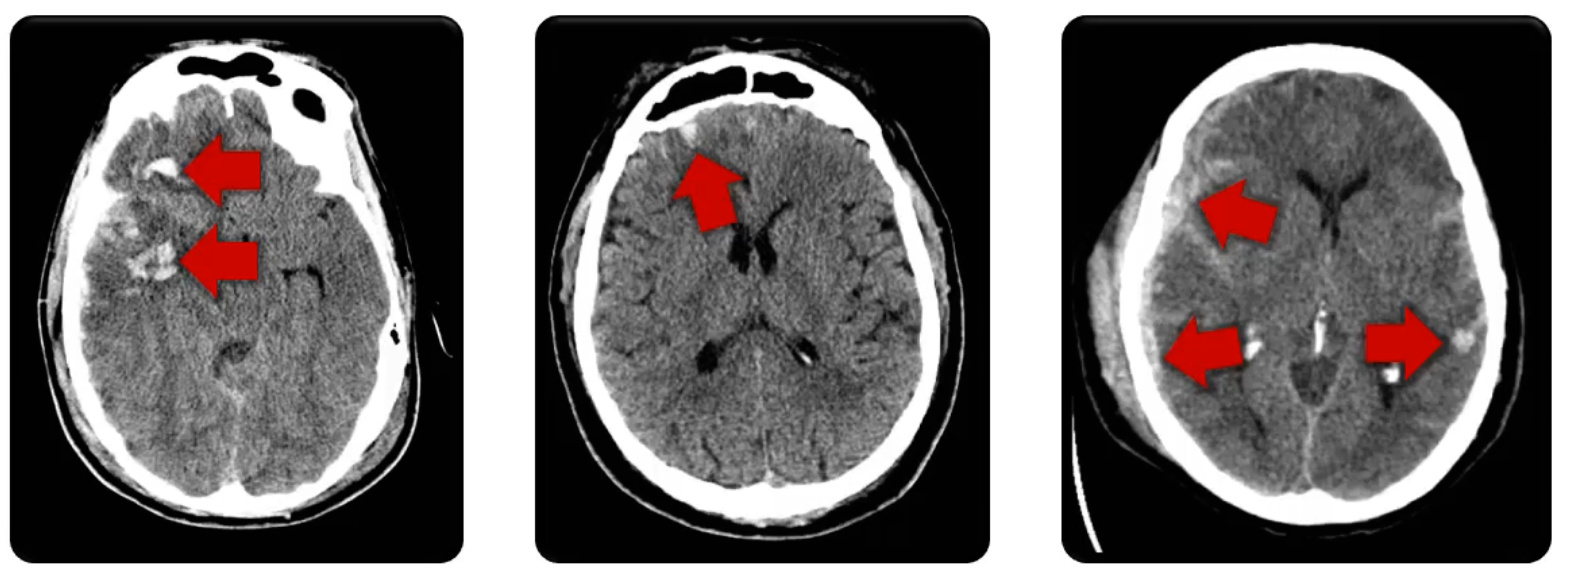

Stroke

The loss of brain fxn. due to a disturbance in the blood flow to the brain.

Ischemic Stroke

Limited blood flow

Thrombosis

Embolism

Stenosis

Pontine Stroke

Hemorrhagic Stroke

Intracranial bleeding

Ruptured vessel

Can result in edema, mass effect, and limited blood supply